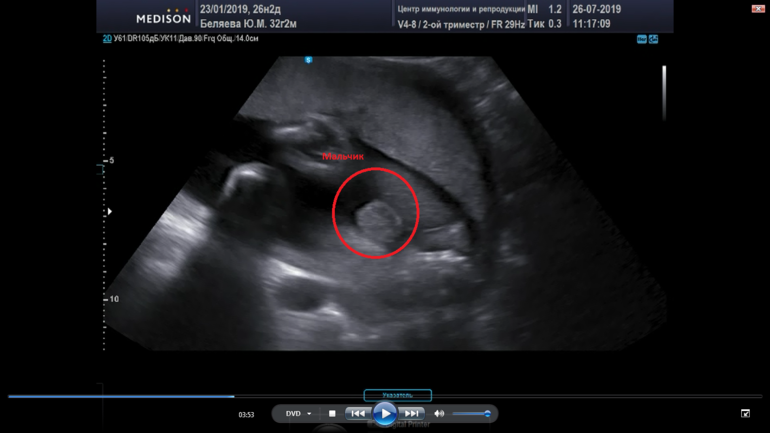

Такая картинка была на 2 скрининге.

А это в 26 недель для себя в ЦИРе. Стоп-кадр с видео.

Ну вот в 26 уже вижу бубенцы, а на втором скрининге просто перчик

Фото с перчиком прям, как у нас один в один😂

Спасибо, так интересно наблюдать как перчик растет🙈😂😂

Ооо,ну у вас на фото перчик уже ни с чем не спутаешь ))Тут без сомнений,даже мошонку видно 🙈